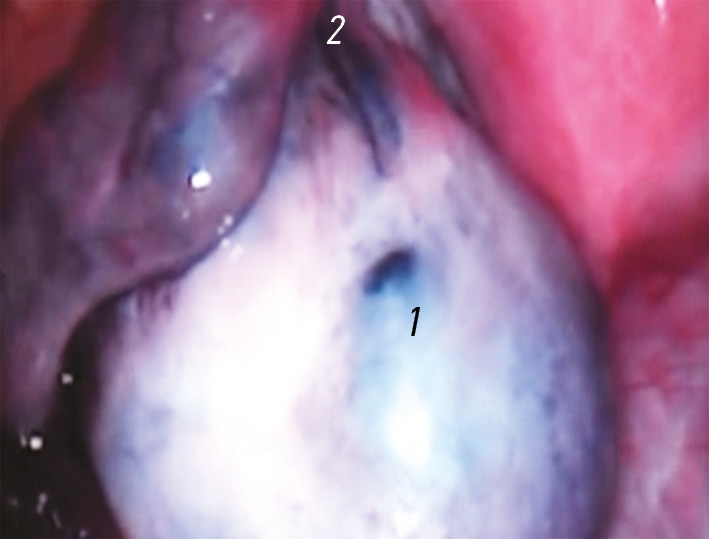

Рис. 1. Ультразвуковое исследование брюшной полости. Стрелка указывает на признаки перекрута правого яичника

Fig. 1. Ultrasound of the abdominal cavity. Arrow, signs of torsion of the right ovaryy

Выполнен ультразвуковой полипозиционный трансабдоминальный осмотр брюшной полости (рис. 1): свободной жидкости не выявлено, мочевой пузырь практически пустой, акустического окна нет, обзор малого таза крайне затруднен. Правый яичник увеличен в размерах (3,0×2,2 см), повышенной эхогенности, фолликулярный рисунок обеднен, кровоток в режиме цветного допплеровского картирования (ЦДК) резко снижен и прослеживается только по периферии. Левый яичник визуализируется частично, видимая часть не изменена. Заключение: косвенные признаки перекрута правого яичника.